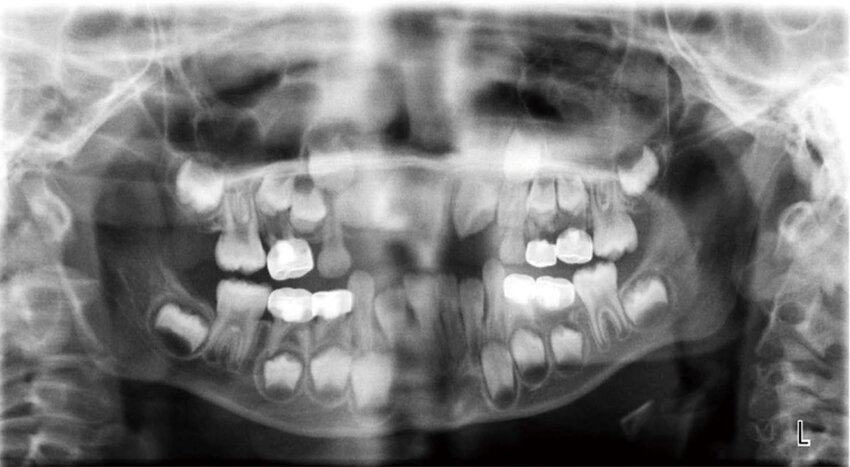

A panoramic radiograph shows a large, blurry, radiopaque shape high on the left side of the image. It appears duplicated and slightly distorted.

Ghost image from jewelry

The inferior portion of the panoramic image is blocked by a large radiopaque area that curves upward like a white hill.

(Lead Apron Artifact) Thyroid collar was used during a panoramic image

A vertical radiopaque band appears in the center of the pano, obscuring the anterior teeth and nasal structures

Patient slumped, causing cervical spine to superimpose

A dark radiolucent band covers the apices of the maxillary teeth on the pano, making them hard to evaluate.

Tongue was not placed against the palate

The panoramic image shows a flat or inverted smile line. The hard palate is superimposed over the maxillary roots.

Chin tipped too far up - reverse smile line

The smile line is exaggerated, the mandibular incisors appear blurry and elongated, and the condyles are cut off

Chin tipped too low

The anterior teeth on the pano appear skinny and blurred, and the spine shadow is more visible.

Patient was positioned too far forward on the bite block

The anterior teeth appear wider and blurry, and the condyles may appear near the edges.

Patient positioned too far back (posterior)